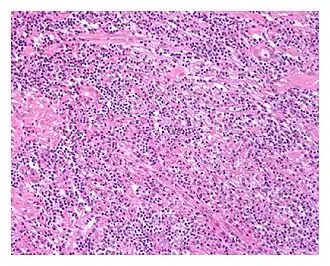

![]() Vista de bajo aumento de la prostatitis relacionada con IgG4. El estroma prostático muestra un denso infiltrado inflamatorio y fibrosis ( H&E , 100x) | ||